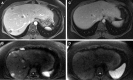

Cancers acquire multiple somatic mutations that can lead to the generation of immunogenic mutation-induced neoantigens. These neoantigens can be recognized by the host's immune system. However, continuous stimulation of immune cells against tumor antigens can lead to immune cell exhaustion, which allows uncontrolled outgrowth of tumor cells. Recently, immune checkpoint inhibitors have emerged as a novel approach to overcome immune cell exhaustion and reactivate antitumor immune responses. In particular, antibodies blocking the exhaustion-mediating programmed death receptor (PD-1)/programmed death receptor ligand (PD-L1) pathway have shown clinical efficacy. The effects were particularly pronounced in tumors with DNA mismatch repair (MMR) deficiency and a high mutational load, which typically occur in the colon and endometrium. Here, we report on a 24-yr-old woman diagnosed with extrahepatic cholangiocarcinoma who showed strong and durable response to the immune checkpoint inhibitor pembrolizumab, although treatment was initiated at an advanced stage of disease. The patient's tumor displayed DNA MMR deficiency and microsatellite instability (MSI) but lacked other features commonly discussed as predictors of response toward checkpoint blockade, such as PD-L1 expression or dense infiltration with cytotoxic T cells. Notably, high levels of HLA class I and II antigen expression were detected in the tumor, suggesting a potential causal relation between functionality of the tumor's antigen presentation machinery and the success of immune checkpoint blockade. We suggest determining MSI status in combination with HLA class I and II antigen expression in tumors potentially eligible for immune checkpoint blockade even in the absence of conventional markers predictive for anti-PD-1/PD-L1 therapy and in entities not commonly linked to the MSI phenotype. Further studies are required to determine the value of these markers for predicting the success of immune checkpoint blockade.